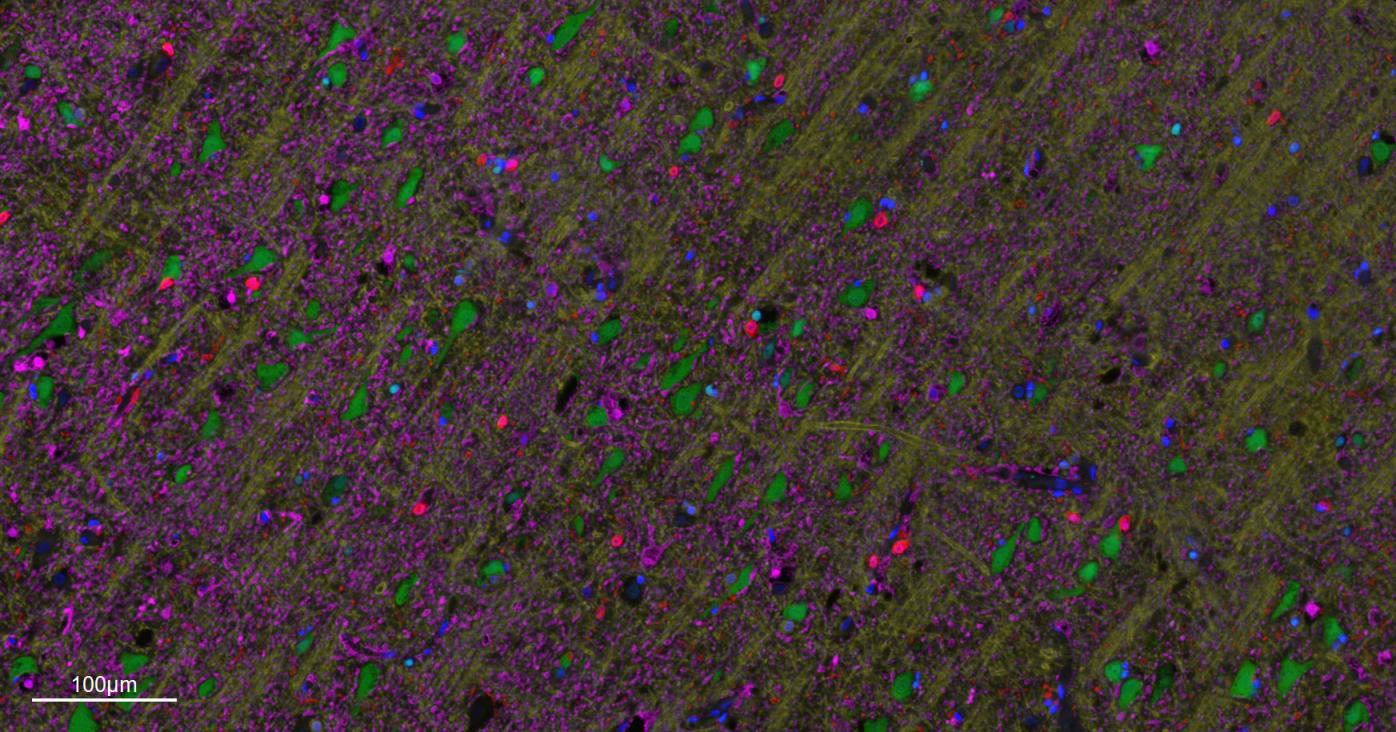

Paraformaldehyde-fixed, paraffin embedded Mouse Cerebrum. Merged staining of anti-GFAP (bsm-42001R; 1:200; pink) anti-AIF1/Iba1 (bsm-54132R; 1:200; red) anti-NeuN (bsm-52268R; 1:200; green) anti-MBP (bsm-33932M; 1:200; yellow) and anti-Olig2 (bsm-61115R; 1:200; light blue) . DAPI (dark blue) was used as a nuclear counter stain.

Paraformaldehyde-fixed, paraffin embedded Human Cerebrum. Merged staining of anti-GFAP (bsm-42001R; 1:200; pink) anti-AIF1/Iba1 (bsm-54132R; 1:200; red) anti-NeuN (bsm-52268R; 1:200; green) anti-MBP (bsm-33932M; 1:200; yellow) and anti-Olig2 (bsm-61115R; 1:200; light blue) . DAPI (dark blue) was used as a nuclear counter stain.

Paraformaldehyde-fixed, paraffin embedded Rat Cerebrum. Merged staining of anti-GFAP (bsm-42001R; 1:200; pink) anti-AIF1/Iba1 (bsm-54132R; 1:200; red) anti-NeuN (bsm-52268R; 1:200; green) anti-MBP (bsm-33932M; 1:200; yellow) and anti-Olig2 (bsm-61115R; 1:200; light blue) . DAPI (dark blue) was used as a nuclear counter stain.